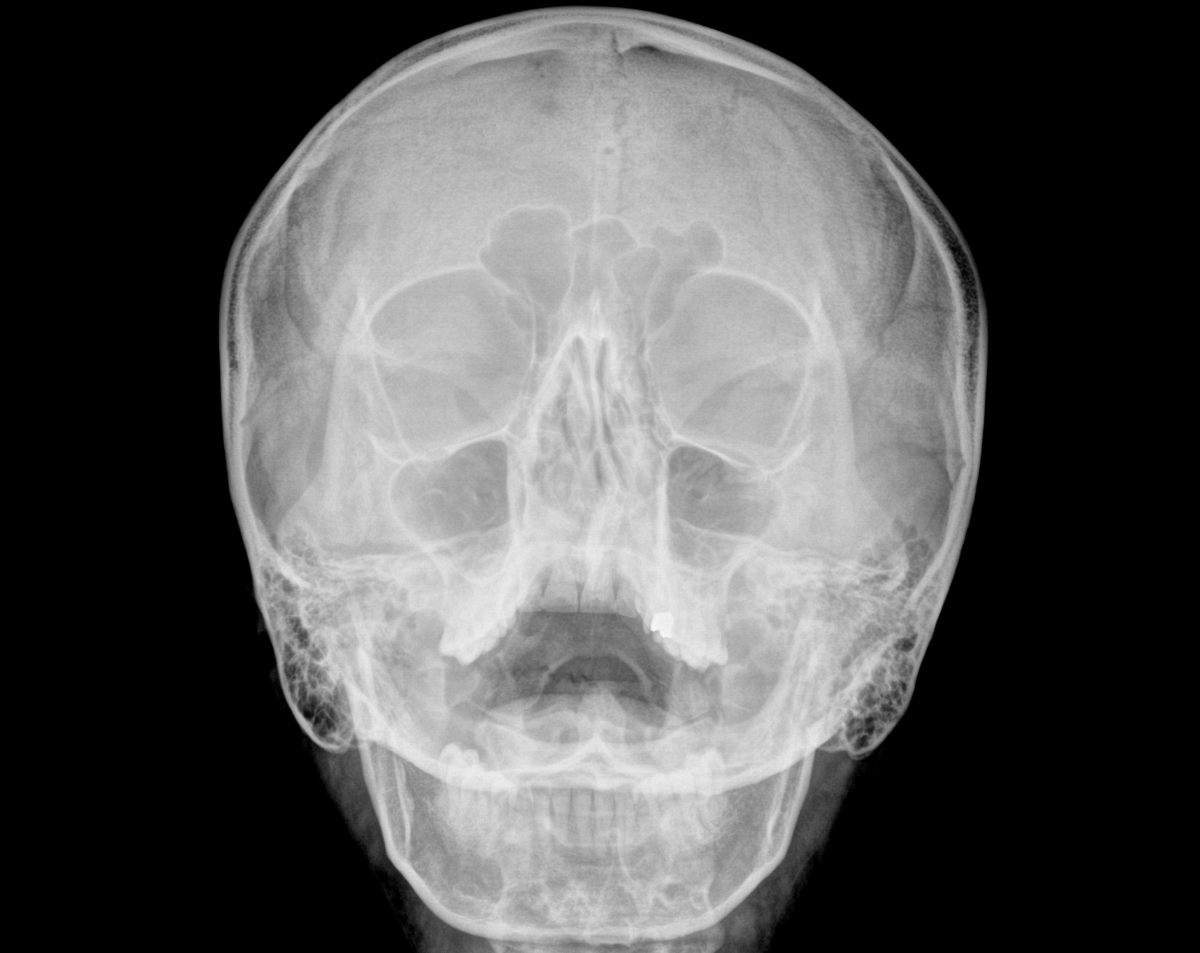

A paranasal sinuses X-ray AH provides a detailed view of the air-filled spaces surrounding your nose and eyes. This simple, fast, and effective imaging test helps physicians diagnose sinus infections, blockages, chronic inflammation, or bone-related abnormalities. At Desert Mobile Medical, we elevate this service by bringing hospital-grade X-ray technology directly to your doorstep—offering comfort, privacy, and speed without the stress of traveling to an imaging center.

A: Yes. We use state-of-the-art, low-dose digital equipment designed to minimize exposure while delivering crystal-clear images.